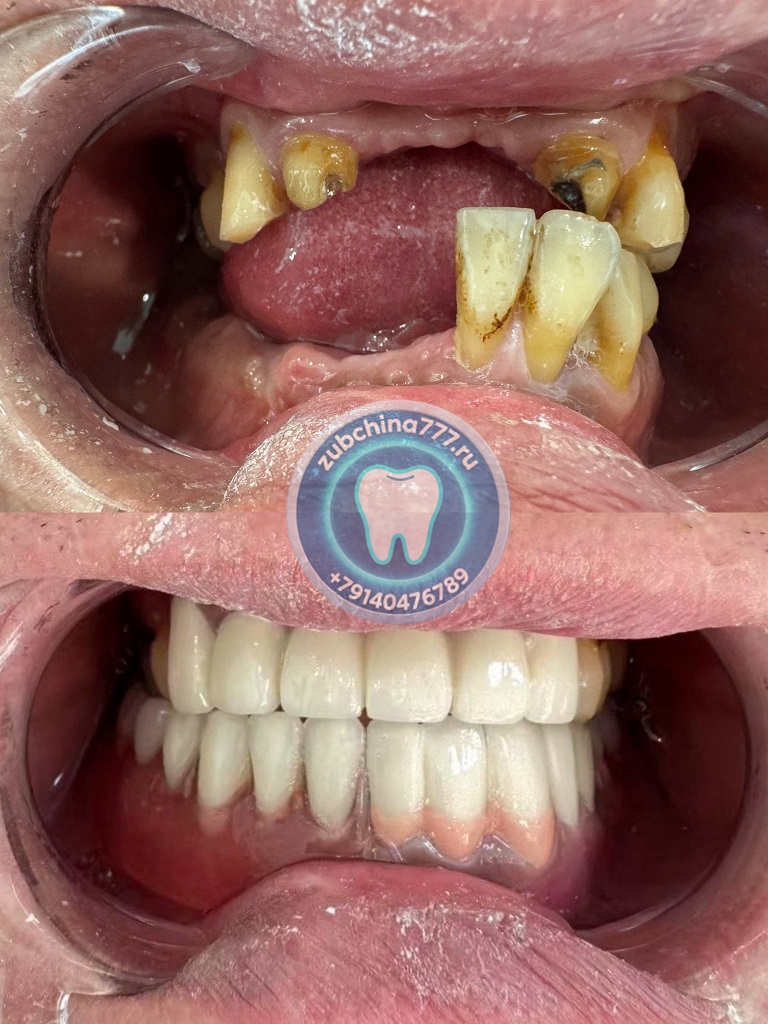

Фотографии пациентов ДО и ПОСЛЕ лечения и протезирования зубов в Хэйхэ